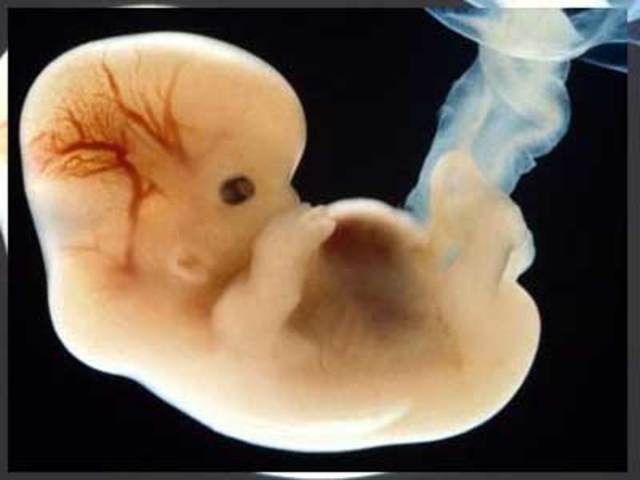

• Comienzan los esbozos de las extremidades, la boca y las mandíbulas son visibles.

Comienzan los esbozos de las extremidades, la boca y las mandíbulas son visibles.

El embrión mide 4mm de longitud; ésta se mide desde el extremo de la cabeza hasta el talón. Cada día la longitud aumenta 1mm hasta el día 55 de gestación. Después crece 1,5mm diario

• 5ta Semana

5ta Semana

En la parte anterior del cuerpo se notan los esbozos de las glándulas mamarias. Las fositas auditivas dejan de verse desde el exterior, para convertirse en vesículas auditivas. El tubo neural está formado por cinco vesículas, es decir que va completando su desarrollo. En esta semana aparecen las "gónadas primitivas",

En el corazón ya se pueden distinguir dos aurículas y dos ventrículos.